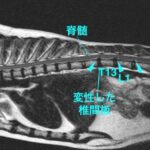

• 【MRI、胸腰部矢状断像、T2強調画像】

• [MR画像 矢状断像 T2強調画像]

#18 頚部脊椎脊髄症(ウォブラー症候群)(飼い主様用)

<症例情報> バーニーズマウンテンドッグ5歳 去勢済みの男の子 主訴:最近首が痛そうで下を…